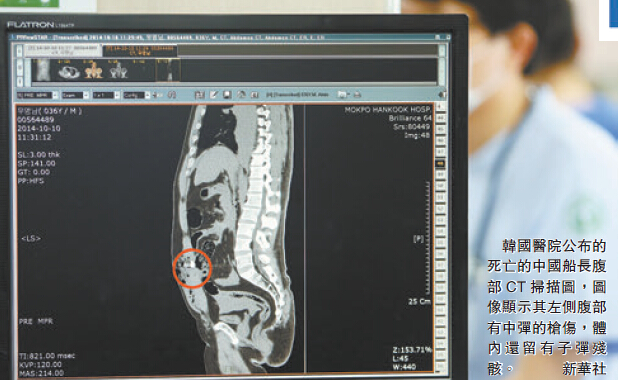

子弹穿透肺部出血

负责救助的韩国医院表示,从CT影像上看,该船长是左侧背部中枪,伤口处有6-7毫米的枪伤,死者肝、肺、肾部受伤,有一枚直径1.6厘米左右的子弹遗留在死者腹中,死者肺部出血严重。不过,有消息人士透露,该船长在抵达医院前已死亡。目前,死亡中国渔船船长身份已确定,名叫宋厚模,山东石岛人。